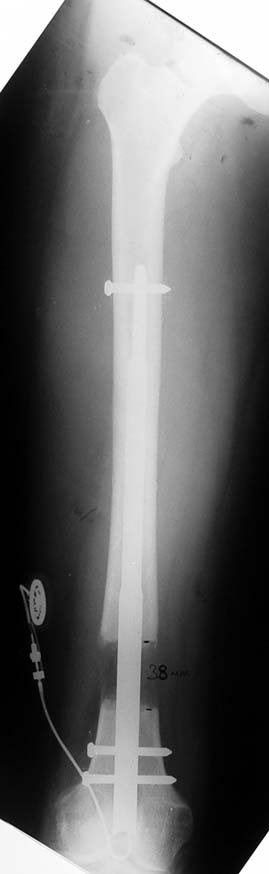

Vaka 2